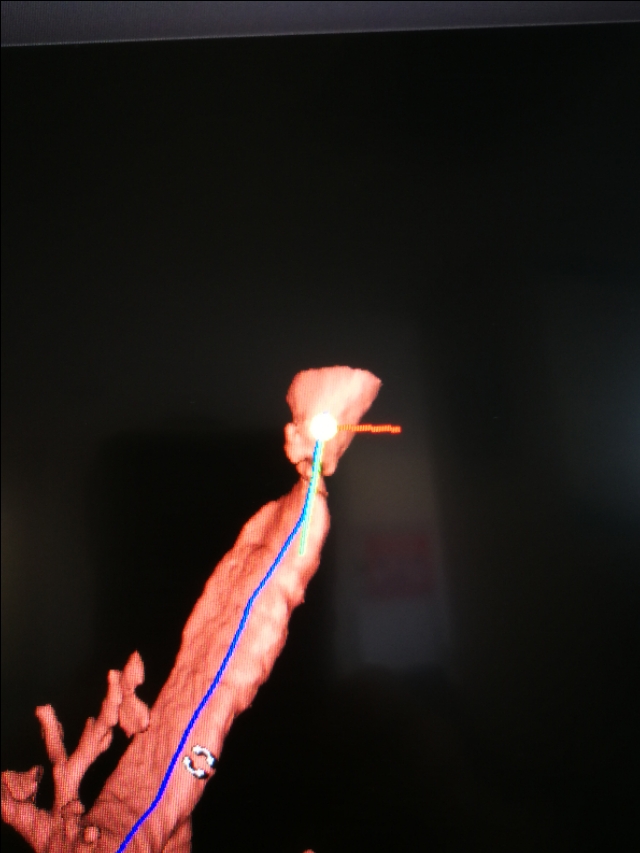

我们想到了一年前他曾经插管上有创呼吸机,可能当时的切口,愈合后形成了瘢痕,瘢痕挛缩导致气道狭窄。

气管镜下可以更直观的看到气管到底多狭窄。只剩下几毫米的小孔了。

最简单的,先用电刀把周边放射状切开,再用球囊扩一扩,就能改善。

麻醉也是很棘手的问题,麻的太浅,病人肯定有痛苦,麻的太深,患者的呼吸又没法保证。再次与麻醉科沟通,备好最细的气管插管,新生儿专用的,导丝备硬的,以防万一。呼吸机,氧气……电刀都调试好。

八点钟方向一刀下去,狭窄处撕开一个口子,还好出血不多。紧接着,又再其他位置放射壮切开。球囊打进水,慢慢的撑起来,这个时间患者是一点呼吸也没有的!时间一秒一秒过,患者血氧轻度下降,停止操作,给氧!指标慢慢好转,反复再做,压力一点点增加。